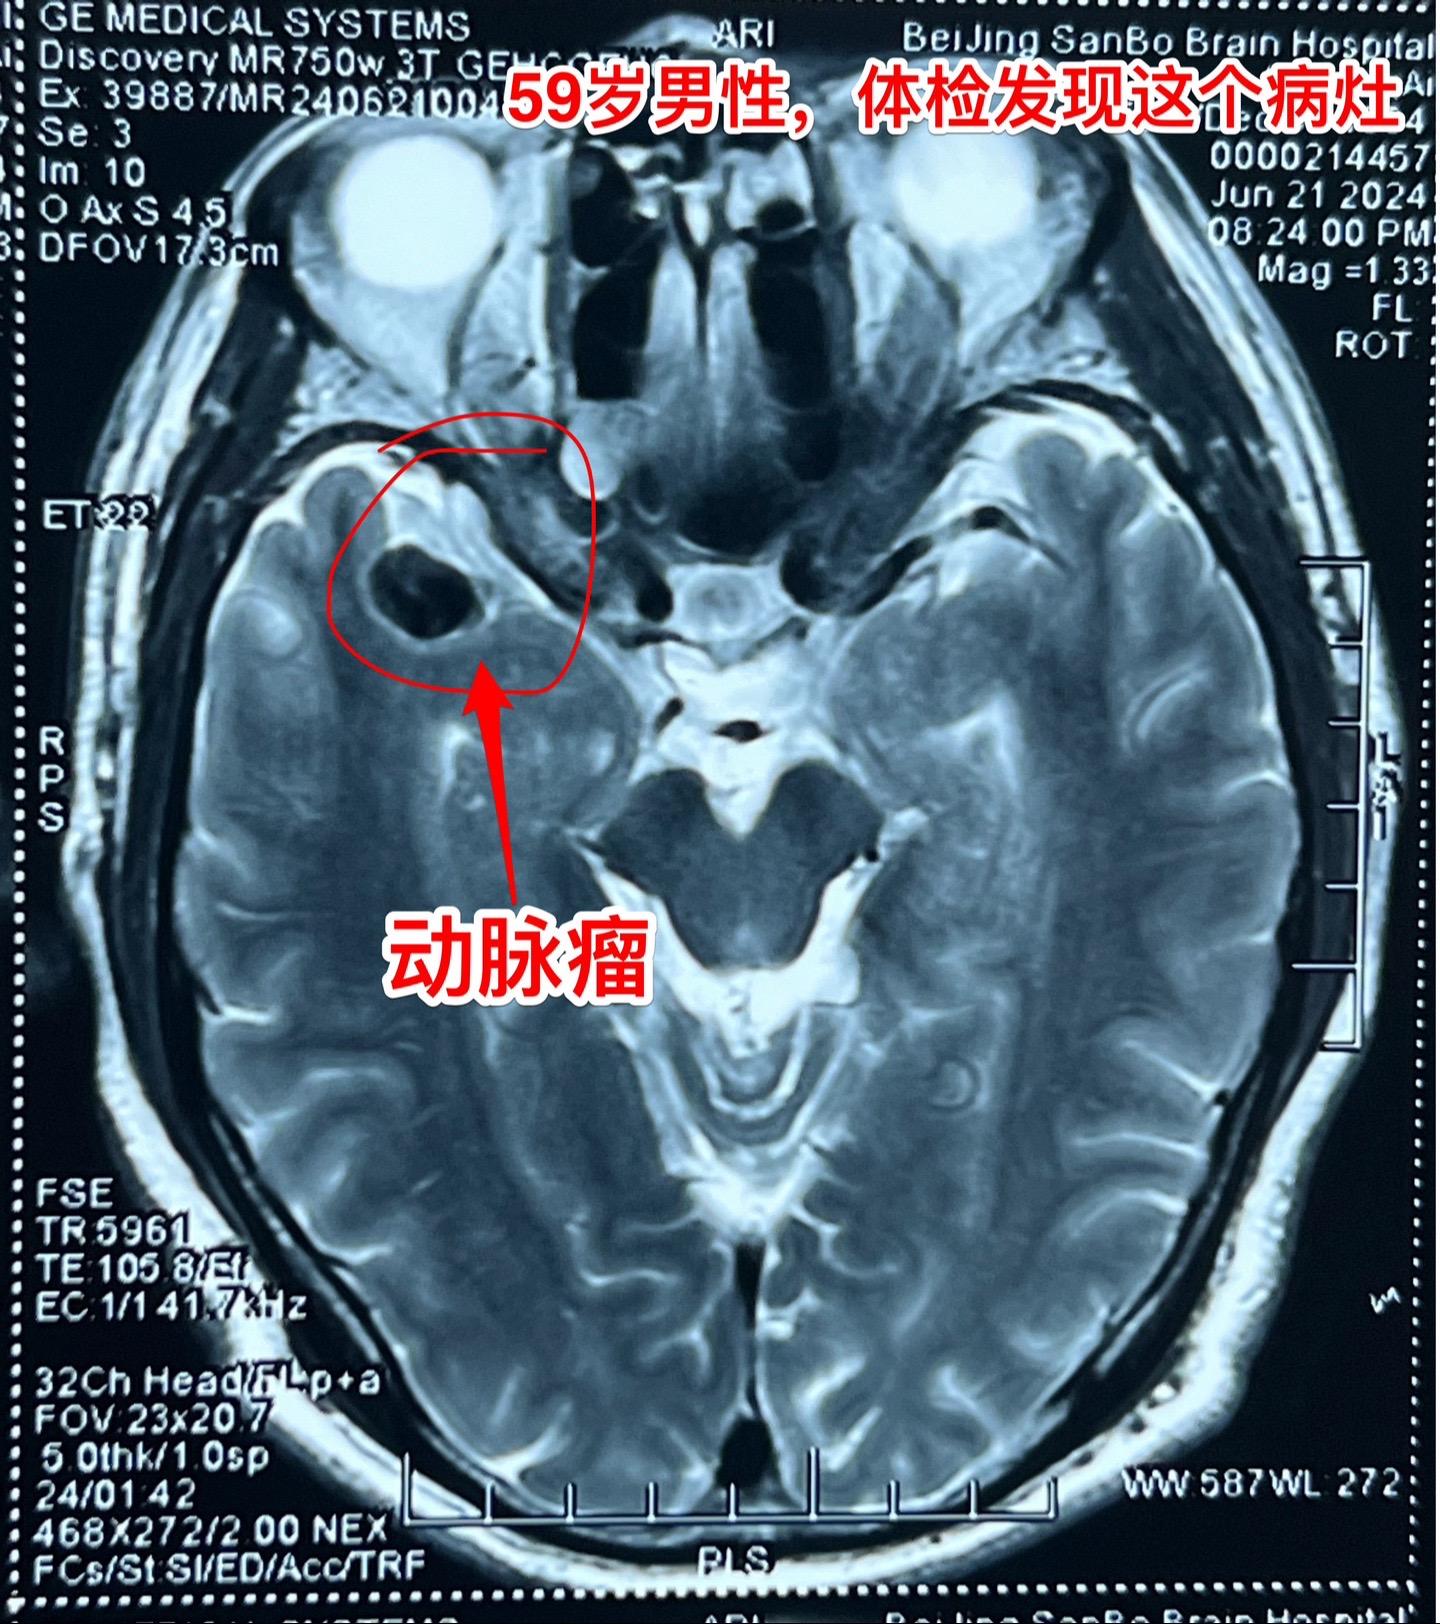

发现未破裂的脑动脉瘤就要作手术吗?慎重!40岁以上的人群中作CTA或者MRA体检筛查脑动脉瘤,发现率是7%!这是未破裂动脉瘤。 未破裂脑动脉瘤的治疗要慎重!要达到国家指南治疗标准才有治疗指征,有治疗指征也不是说必须作手术。 59岁男性,行脑部磁共振检查时发现一个脑动脉瘤,其大小约10x8毫米,位于右侧大脑中动脉,见图。 这个病人从来没有脑部出血病史,这样的动脉瘤需要治疗吗? 这个大脑中动脉动脉瘤直径超过5毫米,根据中国的未破裂脑动脉瘤治疗指南,是